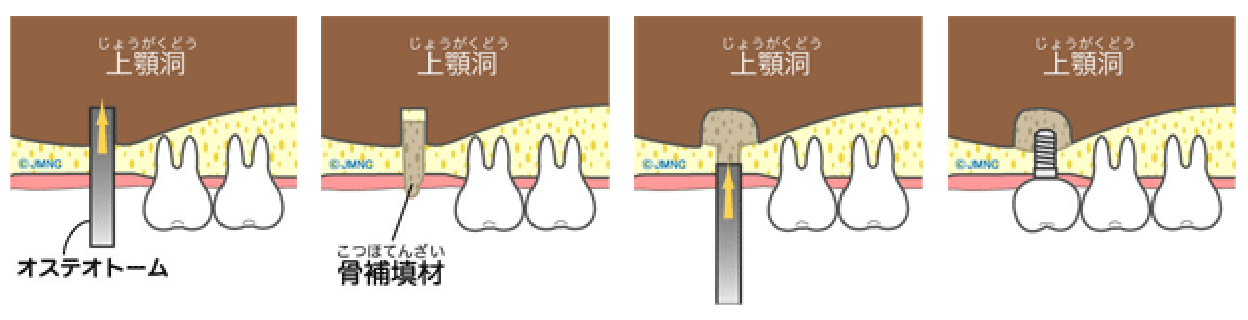

ソケットリフトとサイナスリフト

上顎臼歯部には上顎洞(副鼻腔の一つ)が存在し、骨の高さが足りない場合があります。その場合、上顎洞底部の洞粘膜(シュナイダー膜)を挙上し、挙上によってできた空隙に骨移植を行い骨造成し、インプラントが埋入できるようにします。当院では骨の高さが5~6mm以上の場合にソケットリフト、5~6mm未満の場合にサイナスリフトを行います。つまり、たくさんの骨移植が必要な場合にはサイナスリフトになります。